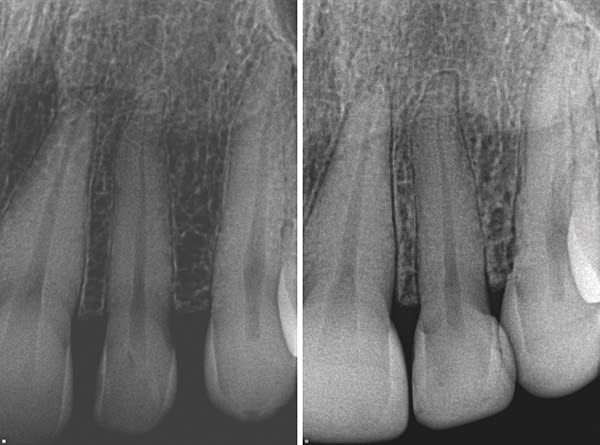

A 46-year-old female patient presented with the chief complaint of disliking the shape, color, and spacing of her front teeth. After conducting online research, the patient was adamant she did not want veneers or traditional bonding but instead preferred Bioclear® composite restorations (Bioclear, bioclearmatrix.com) on her maxillary and mandibular anterior teeth to preserve tooth structure. An intraoral scan using the iTero Element® 2 intraoral scanner (Align Technology, Inc, itero.com) and photographs were taken. It was discussed with the patient that prior to final restorations Invisalign® clear aligner therapy (Align Technology, Inc, invisalign.com) was needed to close all mandibular spacing (eliminating the need for restorations) and partially close the maxillary spacing (improving the height-to-width ratios of the final maxillary restorations). The patient completed Invisalign treatment in 15 weeks and then whitened with Opalescence™ PF 10% whitening gel (Ultradent, ultradent.com). An intraoral scan with the iTero Element 2 scanner was taken for a pre-prosthetic lab wax-up of teeth Nos. 6 through 11. These teeth were restored with full esthetic composite veneers using the Bioclear heated composite injection overmolding technique with Filtek™ Supreme Ultra Universal Restorative White Body paste and flowable (3M Oral Care, 3m.com). No tooth structure was resected. The patient was immediately scanned for Vivera® retainers. She was thrilled with her smile transformation.

Direct composite restorations with the Bioclear method

are minimally invasive, additive, and esthetically natural looking.